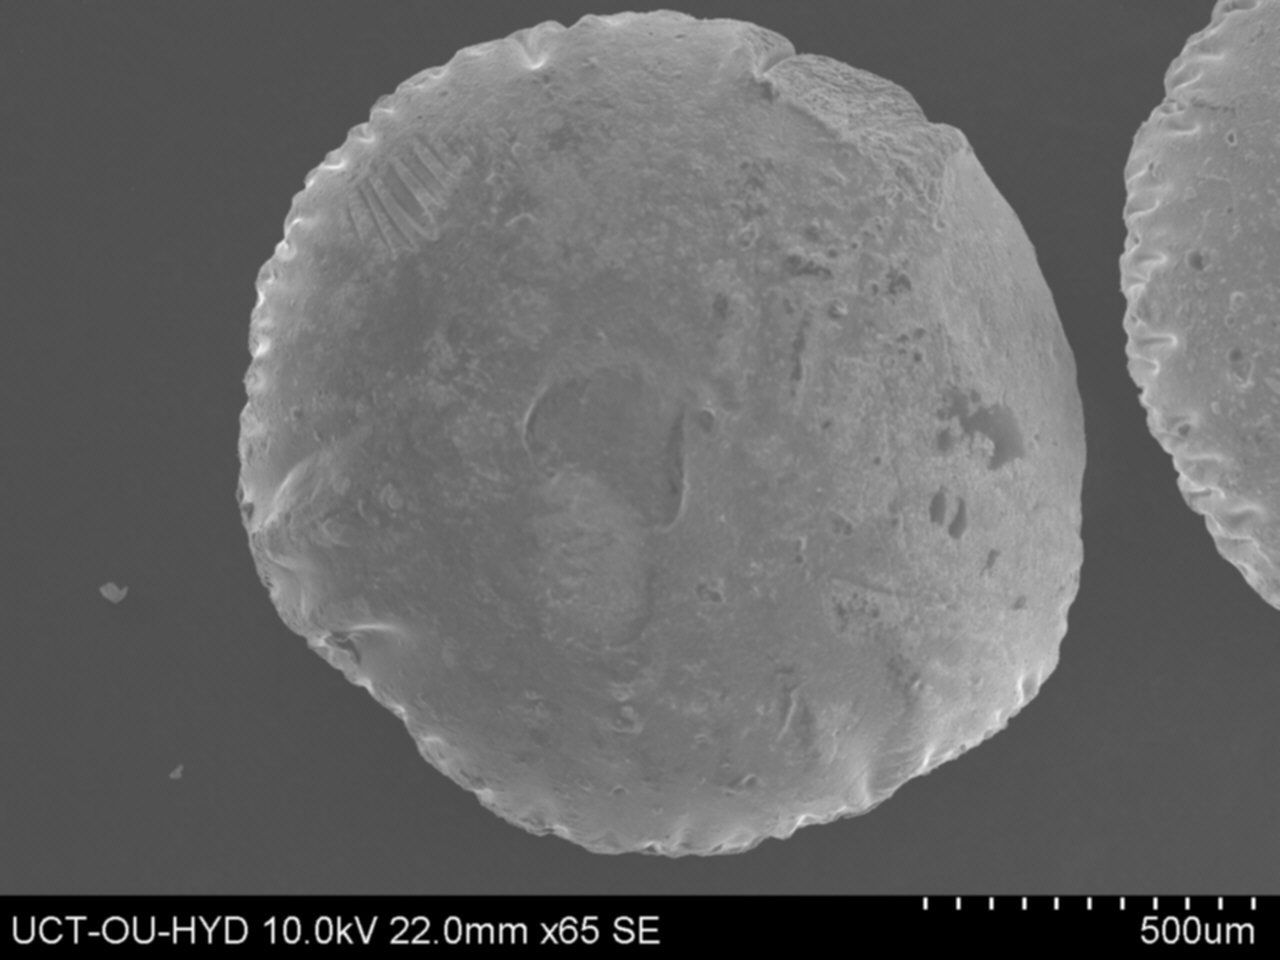

Surface morphology studies of microspheres by scanning electron microscopy

The PS, shape and surface morphology of optimized mucoadhesive microspheres were examined by scanning electron microscopy. Mucoadhesive microspheres were fixed on aluminum studs and coated with gold using a sputter coater SC 502, under vacuum [0.1 mm Hg] and are analyzed using-Model JSM-840 A, Joel. Japan.

Fig. 11: Scanning electron microphotograph of optimized drumstick mucilage-alginate microspheres of lamivudine (F-Opt)

This could be attributed due to the increase in viscosity of polymer solution with the increased proportion of drumstick mucilage, which increased the droplet size of polymer-blend solutions to the cross-linking solutions during preparation. The surface morphological analysis of drumstick mucilage-alginate microspheres of lamivudine was visualized by scanning electron micrograph as shown in fig. 11. The scanning electron micrograph of these microspheres possessed irregular shape without forming agglomeration. Their surface morphologies appeared to have a rough surface with characteristic pores, large wrinkles, and cracks as shown in fig. These pores, cracks, and wrinkles may be due to polymeric gel collapsing during the drying process of microspheres.